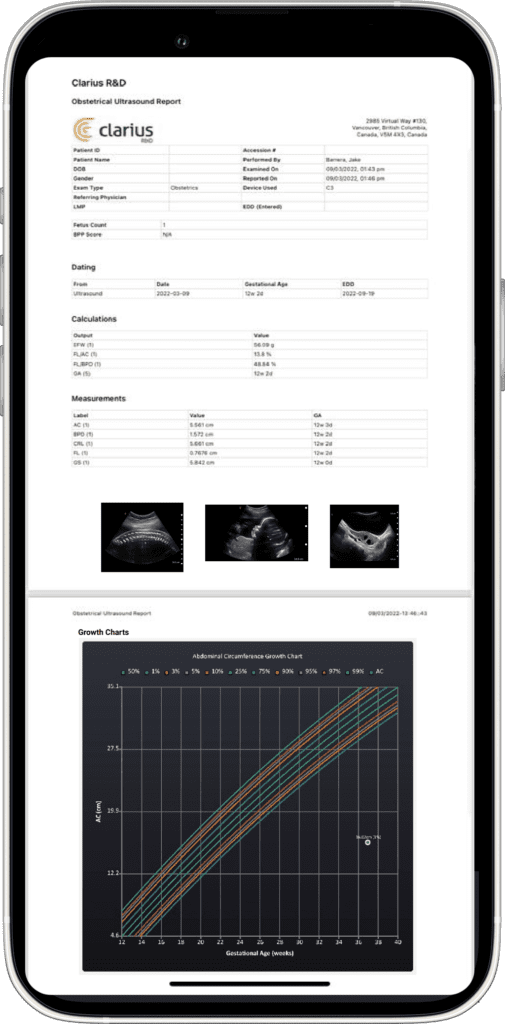

Imagerie Obstétricale Optimisée

I feel more confident with my ultrasound exams since I’ve started using OB AI. I love how the AI makes the app light up when things are perfectly lined up – I can see this really helping both seasoned clinicians and those who are starting their ultrasound journey.